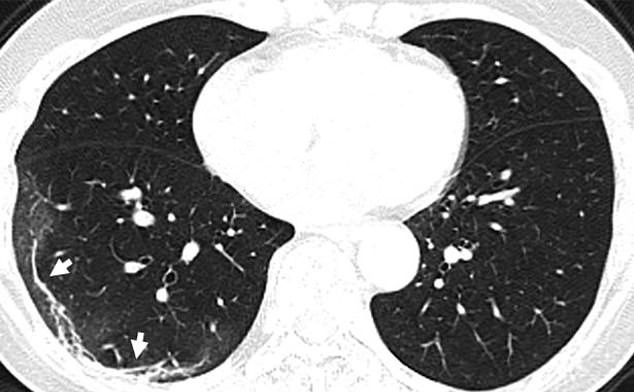

The CT scans of a 45-year-old woman who caught the infection after returning from Japan shows a ‘reversed halo sign’ in the left upper lope of her lung.

The extended white patches were also identified with Middle East respiratory syndrome (MERS) and severe acute respiratory syndrome (SARS).